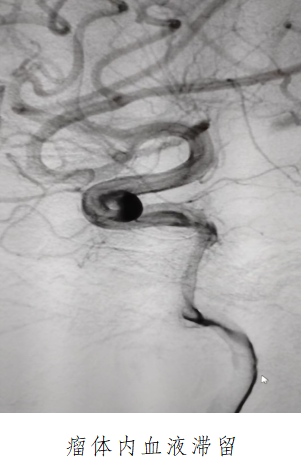

61歲的梁阿姨表情疲倦,因頭暈數(shù)十天來到我院就診,經(jīng)腦血管造影發(fā)現(xiàn)梁阿姨右側(cè)頸內(nèi)動(dòng)脈囊狀動(dòng)脈瘤位于頸內(nèi)動(dòng)脈虹吸彎處,瘤體直徑6毫米,瘤頸寬5毫米,形態(tài)不規(guī)則,此類定時(shí)炸彈如果不積極治療,動(dòng)脈瘤隨時(shí)可能會(huì)破裂,導(dǎo)致蛛網(wǎng)膜下腔出血,可瞬間危及患者生命。

面對(duì)這種特殊情況,我院神經(jīng)介入團(tuán)隊(duì)倪福文主任,朱紅星副主任,陳水洪副主任醫(yī)師等在南方醫(yī)科大學(xué)珠江醫(yī)院神經(jīng)外科中心-腦血管病外科副主任李西鋒教授的帶領(lǐng)下,在麻醉科與介入科通力配合、縝密操作,最終決定打破傳統(tǒng),為梁阿姨實(shí)施“Nuva血流導(dǎo)向密網(wǎng)支架治療顱內(nèi)動(dòng)脈瘤手術(shù),支架貼壁良好,前向血流順暢,載瘤動(dòng)脈血流滯留明顯,不日之內(nèi)完全閉塞。術(shù)后梁姨生命體征平穩(wěn),未出現(xiàn)頭痛、嘔吐及其他神經(jīng)系統(tǒng)癥狀,目前已康復(fù)出院。